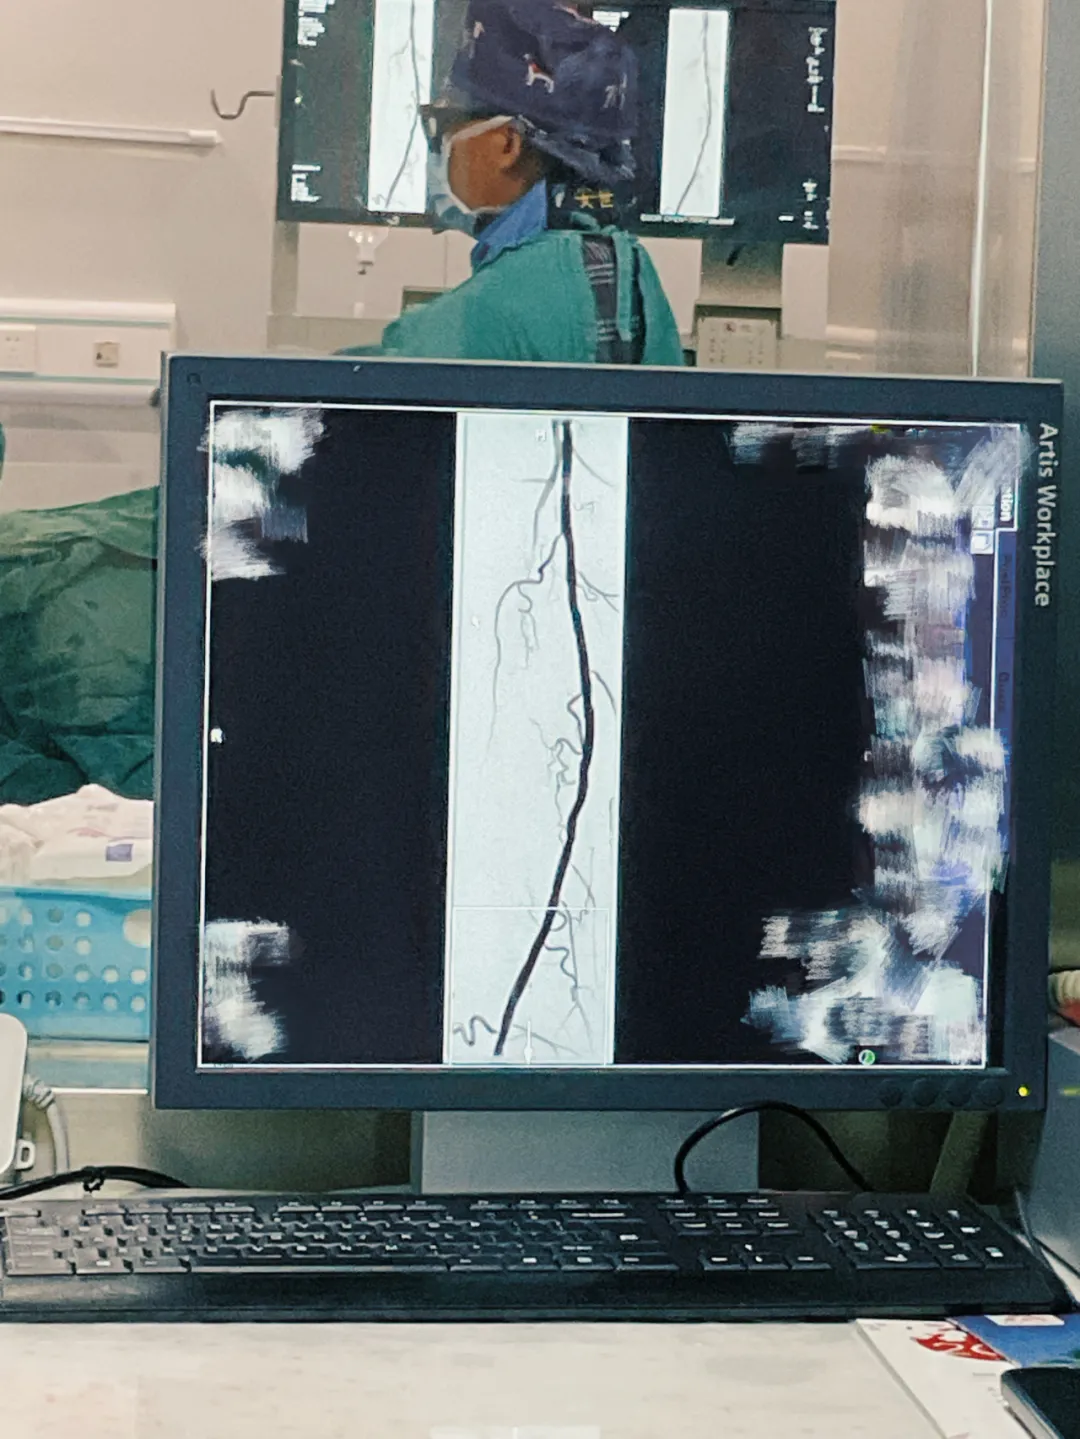

血管外科团队迅速行动,为展先生施行了截趾清创手术,术后配合中药外敷内服,促进创面修复。团队针对其血管堵塞的根本问题,进行了微创介入治疗——采用机械血栓切除系统-导管(Rotarex)对右侧股浅动脉血栓闭塞段行旋切兼容(抽出血栓样物质)后再行下肢动脉球囊扩张成形术,并成功撑开狭窄血管,恢复下肢血流。